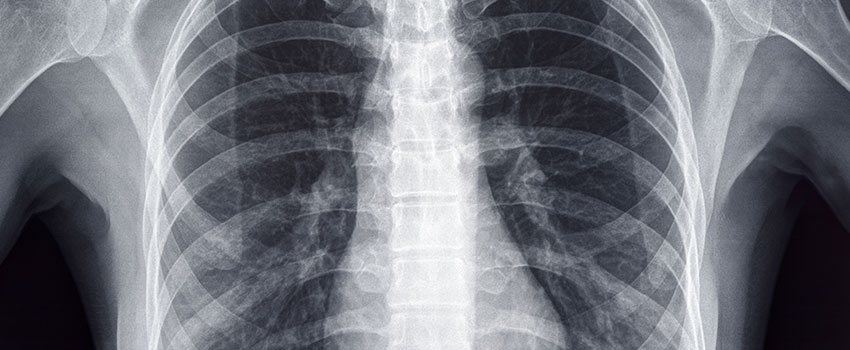

How Do I Know If I Need an X-ray?

Have you recently been injured doing an activity? If so, it can be easy to convince yourself that you can get through the injury at home and that you don’t need an X-ray. While in some cases that may be true, it’s not in others. So, how are you supposed to know when...